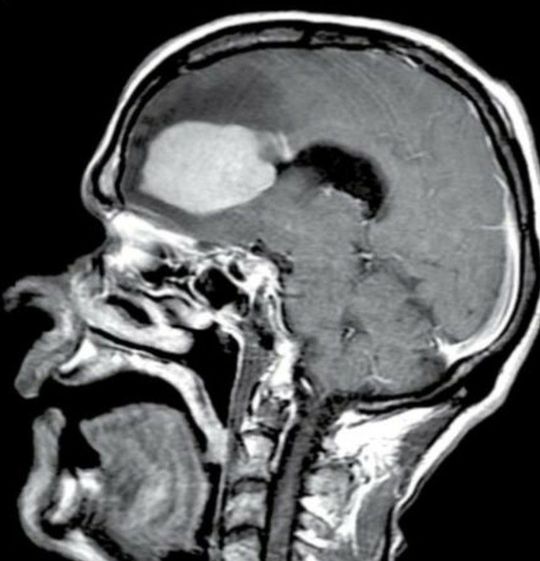

What us the history, and examination finding ?? It could be tumor , vascular malformation , less probably to be henatoma .

Hemorrhage